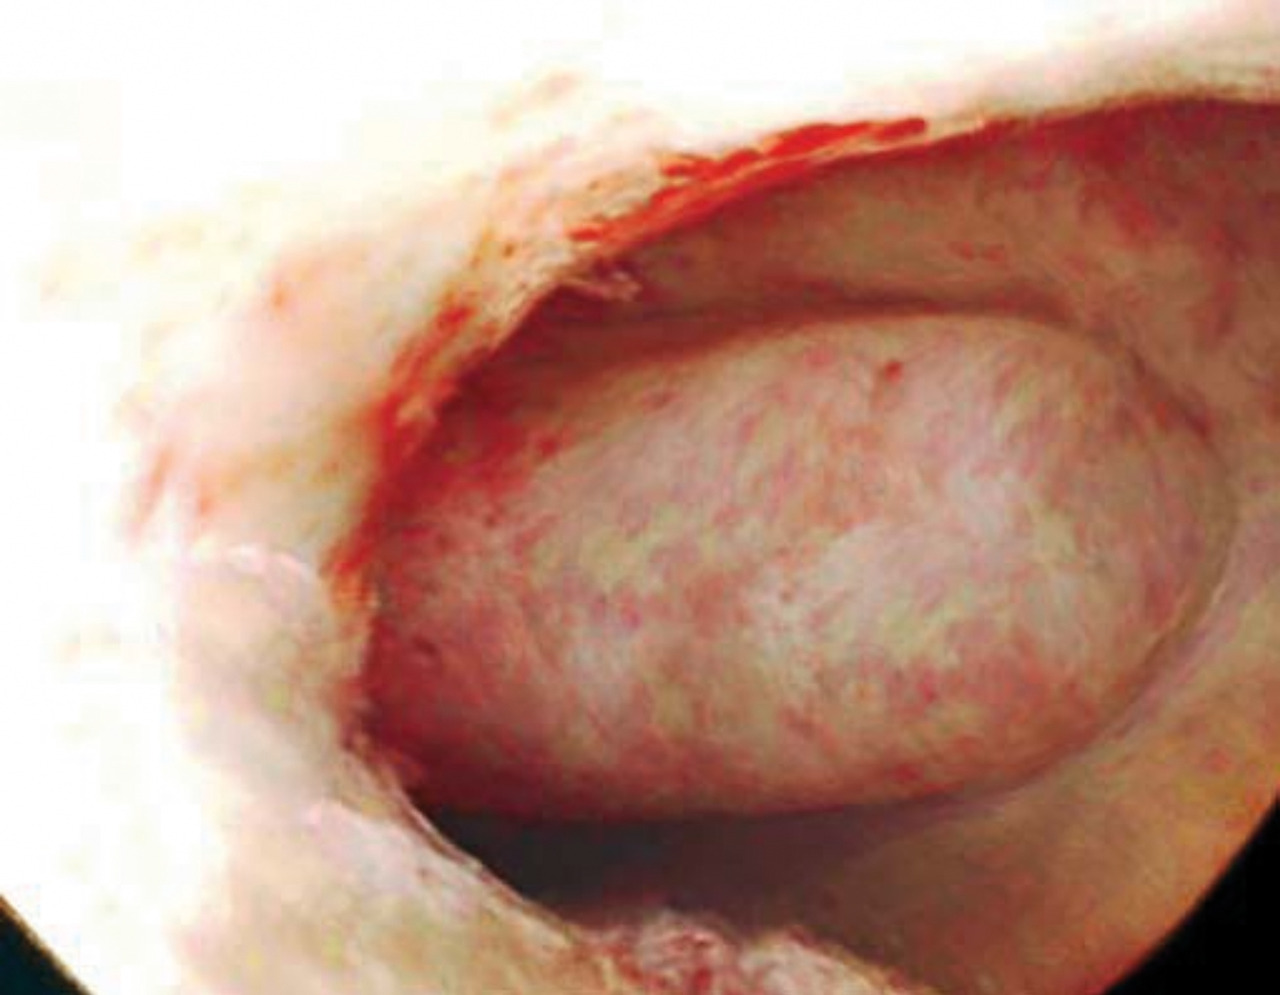

Cancer du col utérin

Le cancer du col utérin doit être évoqué, que les métrorragies soient provoquées par les rapports ou non. L’examen au spéculum recherche un aspect anormal du col, des lésions ulcérantes ou bourgeonnantes (fig. 8) évidentes à l’œil nu sur lesquelles sont pratiquées des biopsies. On réalise un frottis cervicovaginal et un test HPV de dépistage, puis des biopsies au cours d’une colposcopie, à la recherche d’un carcinome épidermoïde, le diagnostic reposant sur l’histologie.